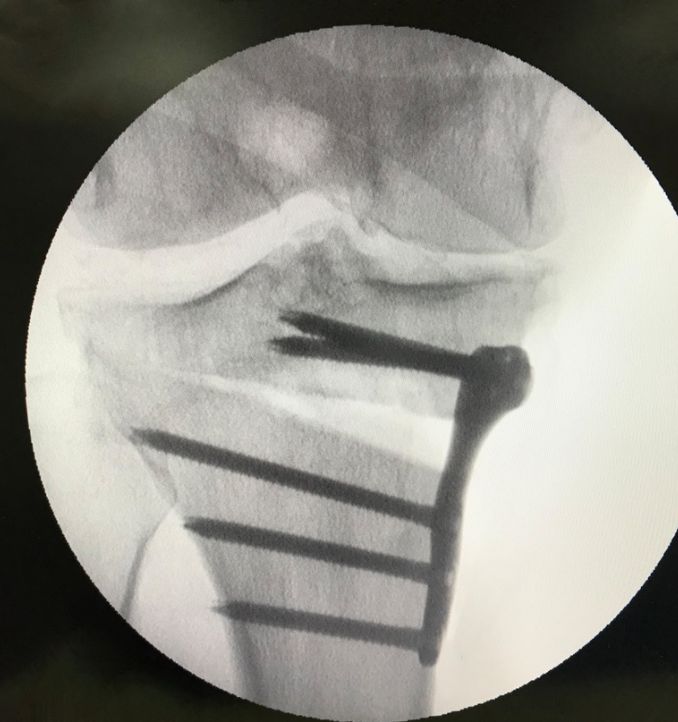

Jestem chirurgiem specjalizującym się w zaawansowanych rekonstrukcjach stawów oraz wydłużaniu kończyn dolnych (limb lengthening and reconstruction surgery). Kompleksowo opiekuję się osobami z problemami o podłożu ortopedycznym oraz neurologicznym, szczególnie dzieci z wadami wrodzonymi i schorzeniami nerwowo-mięśniowymi. Dzięki wieloletniemu doświadczeniu w nowoczesnych technikach rekonstrukcyjnych znacząco udoskonaliłem metody chirurgicznego leczenia dzieci z problemami neurologicznymi, otwierając przed nimi nowe możliwości poprawy funkcjonalności oraz jakości życia. Specjalizujemy się w jednoczasowych wielopoziomowych rekonstrukcjach kończyn (SEMLS) oraz kompleksowych rekonstrukcjach stawów biodrowych, łącząc sprawdzone techniki operacyjne z innowacyjnymi rozwiązaniami. Oprócz leczenia operacyjnego, koordynuje leczenie zachowawcze, obejmujące wielopoziomowe podania toksyny botulinowej (BTX) oraz minimalnie inwazyjne procedury, takie jak SPML (Selective Percutaneous Myofascial Lengthening) czy PERCS (Percutaneous Muscle Lengthening). Każdy pacjent otrzymuje indywidualnie opracowany program terapeutyczny, którego celem jest osiągnięcie najlepszych efektów przy minimalnym obciążeniu. Opiekuję się również pacjentami dorosłymi wymagającymi endopiotezoplastyki stawów oraz ratowaniem kończyn przed amputacją z powodu aktywnej lub przewlekłej infekcji W mojej pracy kluczowe jest podejście holistyczne, które łączy zaawansowane techniki chirurgiczne z terapią zachowawczą, aby zapewnić pacjentom kompleksową opiekę oraz trwałe efekty leczenia. Powierzenie nam zdrowia pacjentów jest dla nas ogromną odpowiedzialnością, a jednocześnie najwyższym zaszczytem. Zakres mojej specjalizacji obejmuje leczenie: 1. Wady wrodzone i rozwojowe kończyn: Hemimelia strzałkowa, niedorozwój kości udowej (CFD – Congenital Femoral Deficiency) – zaawansowane metody rekonstrukcyjne, w tym wydłużanie oraz procedury typu SUPERhip, SUPERankle Brak kości promieniowej i inne deformacje kończyny górnej – zabiegi ulnaryzacji, pollicyzacji, korekcji osi Mnogie wyrośla chrzęstno-kostne (MHE) – chirurgiczna korekcja deformacji i zapobieganie wtórnym ograniczeniom ruchomości Wrodzony staw rzekomy kości piszczelowej (CPT) – rekonstrukcja podudzia metodą CPT Xunion 2. Zaburzenia osi i długości kończyn: Skrócenia kończyn – techniki wydłużania z zastosowaniem gwoździ teleskopowych, aparatów Ilizarowa oraz STRYDE i PRECICE Zaburzenia osi kończyn (koślawość, szpotawość, rotacje) – korekcje wielopłaszczyznowe, osteotomie oraz stabilizacja z użyciem aparatów zewnętrznych i gwoździ wewnętrznych 3. Neuroortopedia – leczenie pacjentów z zaburzeniami neurologicznymi: Mózgowe porażenie dziecięce (MPD) – operacje zmniejszające spastyczność, korekcje stawów oraz zabiegi wielopoziomowe poprawiające funkcję chodu Przepuklina oponowo-rdzeniowa (spina bifida) – leczenie deformacji stóp i kończyn dolnych, stabilizacja stawów Artrogrypoza – wieloetapowe leczenie chirurgiczne poprawiające zakres ruchu i funkcjonalność kończyn 4. Zakażenia i zaburzenia zrostu kostnego: Osteomyelitis (zakażenia kości i szpiku) – leczenie chirurgiczne i antybiotykoterapia celowana Zaburzenia zrostu kostnego, brak zrostu (non-union, mal-union) – nowoczesne techniki transportu kostnego, przeszczepów i stabilizacji 5. Rekonstrukcja dużych stawów i leczenie deformacji: Endoprotezoplastyka biodra, kolana i stawu skokowego – zarówno w przypadkach zwyrodnieniowych, jak i pourazowych Choroba Legg-Calvé-Perthesa – metody operacyjne poprawiające ukrwienie głowy kości udowej i ograniczające deformację Złuszczenie głowy kości udowej (SCFE – Slipped Capital Femoral Epiphysis) – leczenie za pomocą zmodyfikowanej metody Dunna, pozwalającej na anatomiczną rekonstrukcję biodra i zachowanie funkcji stawu Dysplazje szkieletowe – interdyscyplinarne podejście do leczenia deformacji i ograniczeń funkcjonalnych 6. Leczenie stopy cukrzycowej i deformacji stóp: Stopa cukrzycowa – nowoczesne techniki rekonstrukcji stopy, zapobieganie amputacji Deformacje stopy (np. stopa końsko-szpotawa, płasko-koślawa, stopa sierpowata) – korekcja chirurgiczna i indywidualne podejście do biomechaniki chodu 7. Chirurgia urazowa dzieci i dorosłych: Leczenie złamań z zastosowaniem minimalnie inwazyjnych technik operacyjnych Rekonstrukcja kończyn po urazach, w tym ratowanie kończyny zagrożonej amputacją Stabilizacja wewnętrzna i zewnętrzna złamań patologicznych oraz pourazowych 8. Osseointegracja - zaopatrzenie pacjentów po amputacji poprzez korekcję kikuta lub aplikację osseointegracji do kości powyżej lub poniżej kolana wraz z zaopatrzeniem prtotetycznym 9. Wydłużanie kosmetyczne kończyn dolnych i górnych. Wykonujemy jednoczasowe operacje zarówno wydłużania kości udowych i piszczelowych jako jedyny ośrodek w Europie. Efekt jaki możemy uzyskać to 10-12 cm zwiększenia wzrostu. Wierzę, że najlepsze efekty leczenia można osiągnąć dzięki współpracy grona specjalistów, kierując się zasadą pacjentocentryzmu, która stawia potrzeby pacjenta w centrum procesu terapeutycznego.. Dlatego każda konsultacja odbywa się w interdyscyplinarnym zespole, w skład którego wchodzą ortopedzi, fizjoterapeuci, ortotycy i terapeuci zajęciowi. Pierwsza wizyta trwa około 1,5 godziny i obejmuje szczegółową ocenę stanu zdrowia oraz opracowanie planu leczenia chirurgicznego. W naszym instytucie działamy na podstawie indywidualnie opracowanych dla każdej jednostki chorobowej protokołów leczenia operacyjnego oraz postępowania fizjoterapeutycznego, których jestem współautorem. Dzięki temu zapewniamy spójne, kompleksowe i skuteczne podejście terapeutyczne, dostosowane do specyfiki danej choroby i indywidualnych potrzeb pacjenta. Zapraszam na konsultacje ortopedyczne, neuroortopedyczne oraz deformacyjne.